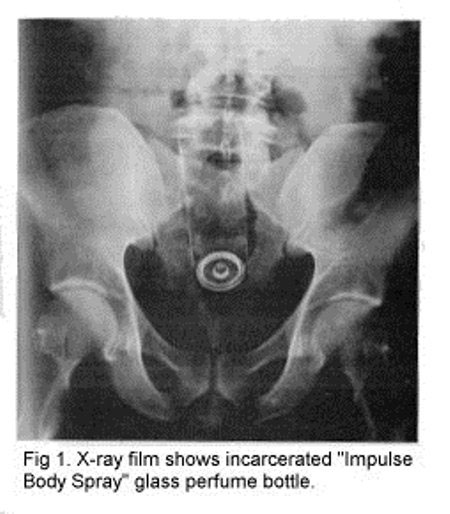

5. Botol Parfum

Seorang pengacara berusia 39 tahun masuk ke rumah sakit gara-gara sebuah botol parfum tersangkut di anusnya. Ini bukan pertama kalinya ia memasukkan benda ini, namun kali ini, barang ini tersangkut. Ouch!